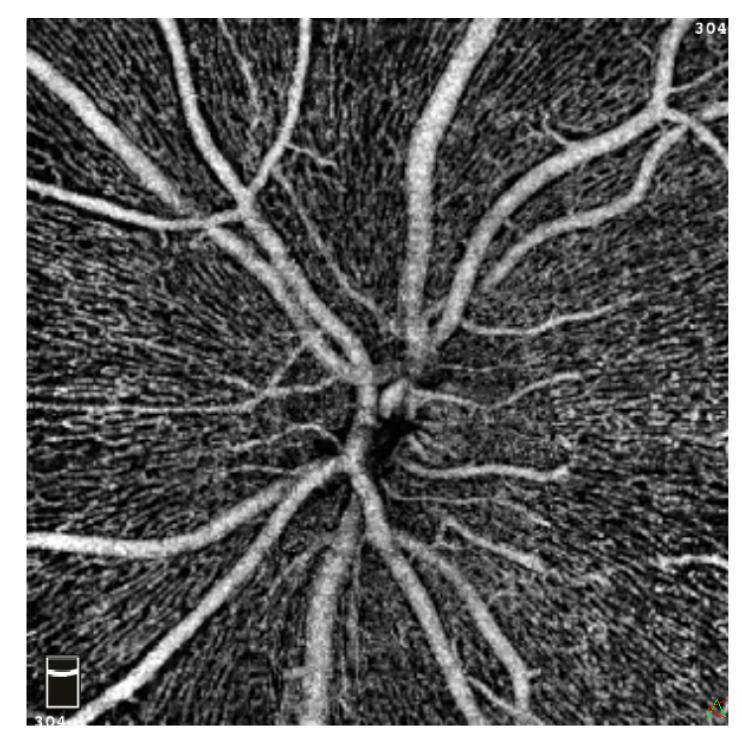

Hemodialysis (HD) is known to affect ocular blood flow. This case-control study aims to evaluate macular and peripapillary vasculature in patients with end-stage renal disease (ESRD) receiving HD in comparison to matched controls. A total of 24 eyes of 24 ESRD patients receiving HD and 24 eyes of 24 healthy, age- and gender-matched control subjects were prospectively included in this study. Optical coherence tomography angiography was used to image the superficial (SCP), deep (DCP), and choriocapillary (CC) macular vascular plexus, as well as the radial peripapillary capillaries (RPC) of the optic disc. In addition, retinal thickness (RT) and retinal volume (RV) were compared between both groups. Flow density (FD) values of each retinal layer and data of parameters related to the foveal avascular zone (FAZ), as well as RT and RV, were analyzed using Mann-Whitney U tests. There was no significant difference in FAZ parameters between the two groups. Whole en face FD of the SCP and CC was noticeably reduced in the HD group in comparison to the control group. FD was negatively correlated with the duration of HD treatment. RT and RV were significantly smaller in the study group than in controls. Retinal microcirculation appears altered in patients with ESRD undergoing HD. Concurrently, the DCP appears more resilient towards hemodynamic changes in comparison to the other microvascular retinal layers. OCTA is a useful, non-invasive tool to investigate retinal microcirculation in ESRD patients.

已知血液透析(HD)会影响眼部血流。本病例对照研究旨在评估接受HD治疗的终末期肾病(ESRD)患者与匹配对照组相比的黄斑和视乳头周围血管系统。本研究前瞻性纳入了24例接受HD治疗的ESRD患者的24只眼以及24名年龄和性别匹配的健康对照者的24只眼。使用光学相干断层扫描血管造影术对浅表(SCP)、深层(DCP)和脉络膜毛细血管(CC)黄斑血管丛以及视盘的放射状视乳头周围毛细血管(RPC)进行成像。此外,比较了两组之间的视网膜厚度(RT)和视网膜体积(RV)。使用Mann-Whitney U检验分析各视网膜层的血流密度(FD)值以及与中心凹无血管区(FAZ)相关的参数数据,以及RT和RV。两组之间的FAZ参数无显著差异。与对照组相比,HD组SCP和CC的全层FD明显降低。FD与HD治疗持续时间呈负相关。研究组的RT和RV显著小于对照组。接受HD治疗的ESRD患者的视网膜微循环似乎发生了改变。同时,与其他视网膜微血管层相比,DCP似乎对血流动力学变化更具弹性。光学相干断层扫描血管造影术(OCTA)是一种用于研究ESRD患者视网膜微循环的有用的非侵入性工具。